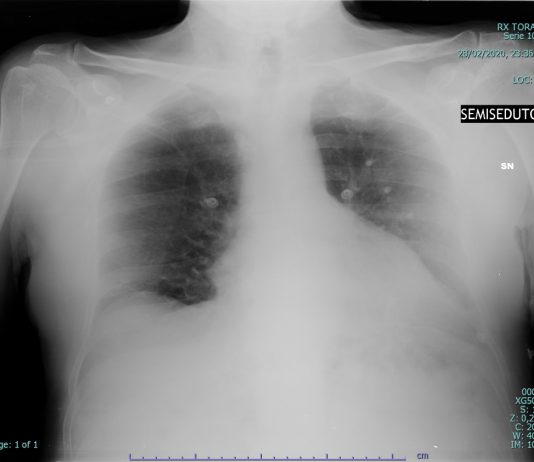

65-years-old male

patient presented to the ED with fever and cough.

Blood test: C-PR 70,99 (< 5) LDH 326 (< 225).